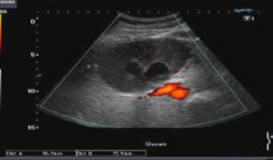

pyogenic abscess

ameobic abscess